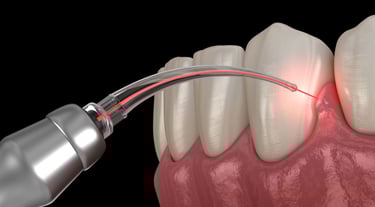

Laser Treatments

Laser dentistry potentially offers a more comfortable treatment option for a number of dental procedures involving hard or soft tissue compared to drills and other non-laser tools.

LASER stands for “light amplification by the stimulated emission of radiation.” The instrument creates light energy in a very narrow and focused beam. This laser light produces a reaction when it hits tissue, allowing it to remove or shape the tissue.

How are laser treatments performed?

The two main types of procedures used for laser dentistry are hard tissue and soft tissue procedures. Hard tissue refers to the teeth, and soft tissue refers to the gums.

Common soft tissue procedures include: